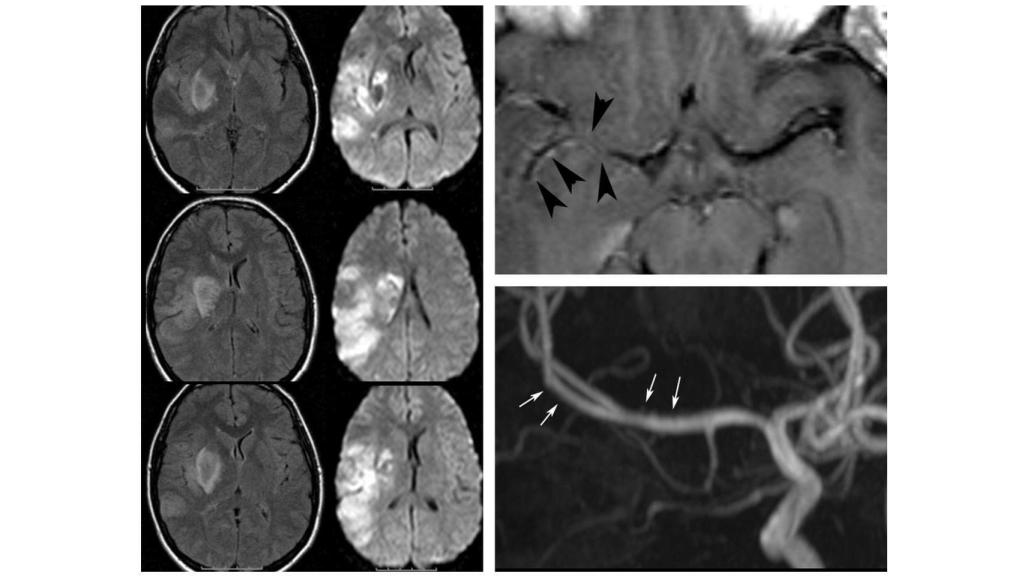

Destrucción de la materia blanca en un consumidor crónico de heroína, lo que provoca deterioro cognitivo. Ajnr.org